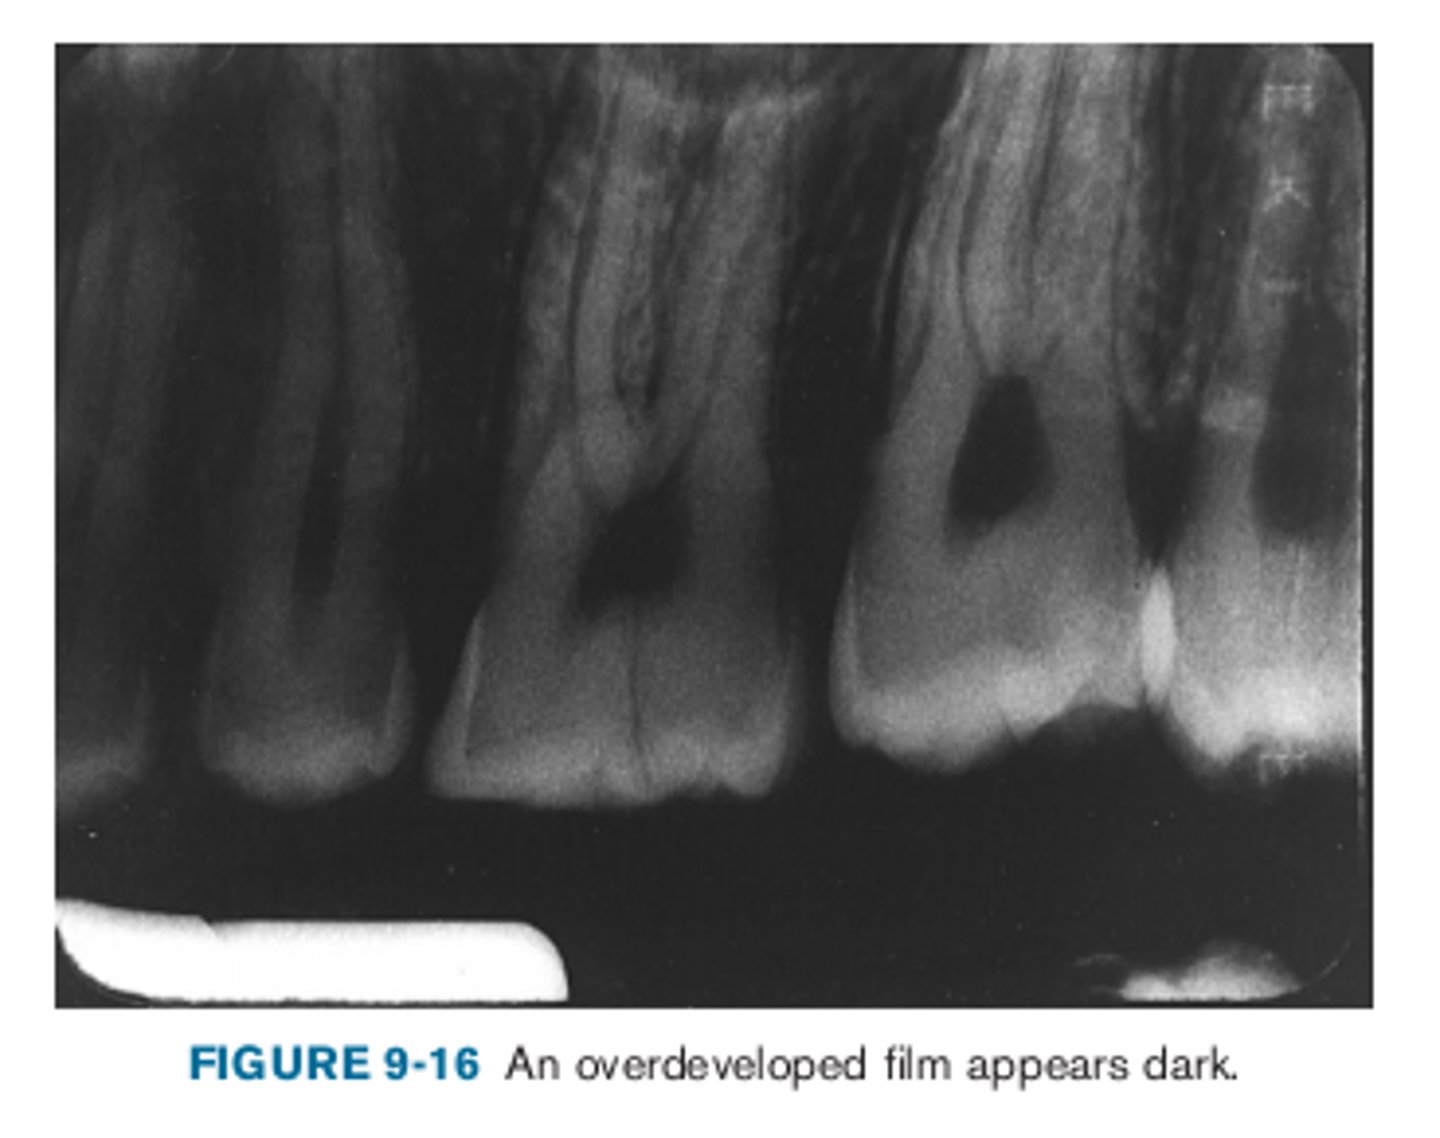

overdeveloped film

Dark appearance due to:

•Excessive developing time

•Developer solution too hot

•Inaccurate timer or thermometer

•Concentrated developer solution

<p>Dark appearance due to:</p><p>•Excessive developing time</p><p>•Developer solution too hot</p><p>•Inaccurate timer or thermometer</p><p>•Concentrated developer solution</p>